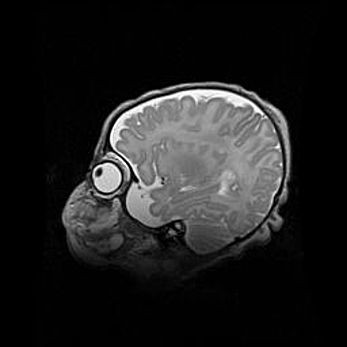

Мальформация Денди-Уокера. Киста задней черепной ямки.

Агенезия мозолистого тела.

Возраст: 2,5 месяца

Вес: 2420 г

Пол: женский

Окружность головы: 37 см

Срок гестации: 32 недели

Мальформация Денди—Уокера — редкий вид патологии ЦНС, представляющий собой врожденный порок развития каудального отдела ствола и червя мозжечка, ведущий к неполному раскрытию срединной (Мажанди) и латеральных (Лушка) апертур IV желудочка мозга. Для этогно синдрома характерна триада симптомов: гипотрофия червя мозжечка и/или полушарий мозжечка, кисты задней черепной ямки, гидроцефалия различной степени. В 70% случаев порок сочетается и с другими аномалиями головного мозга, в частности с агенезией мозолистого тела.